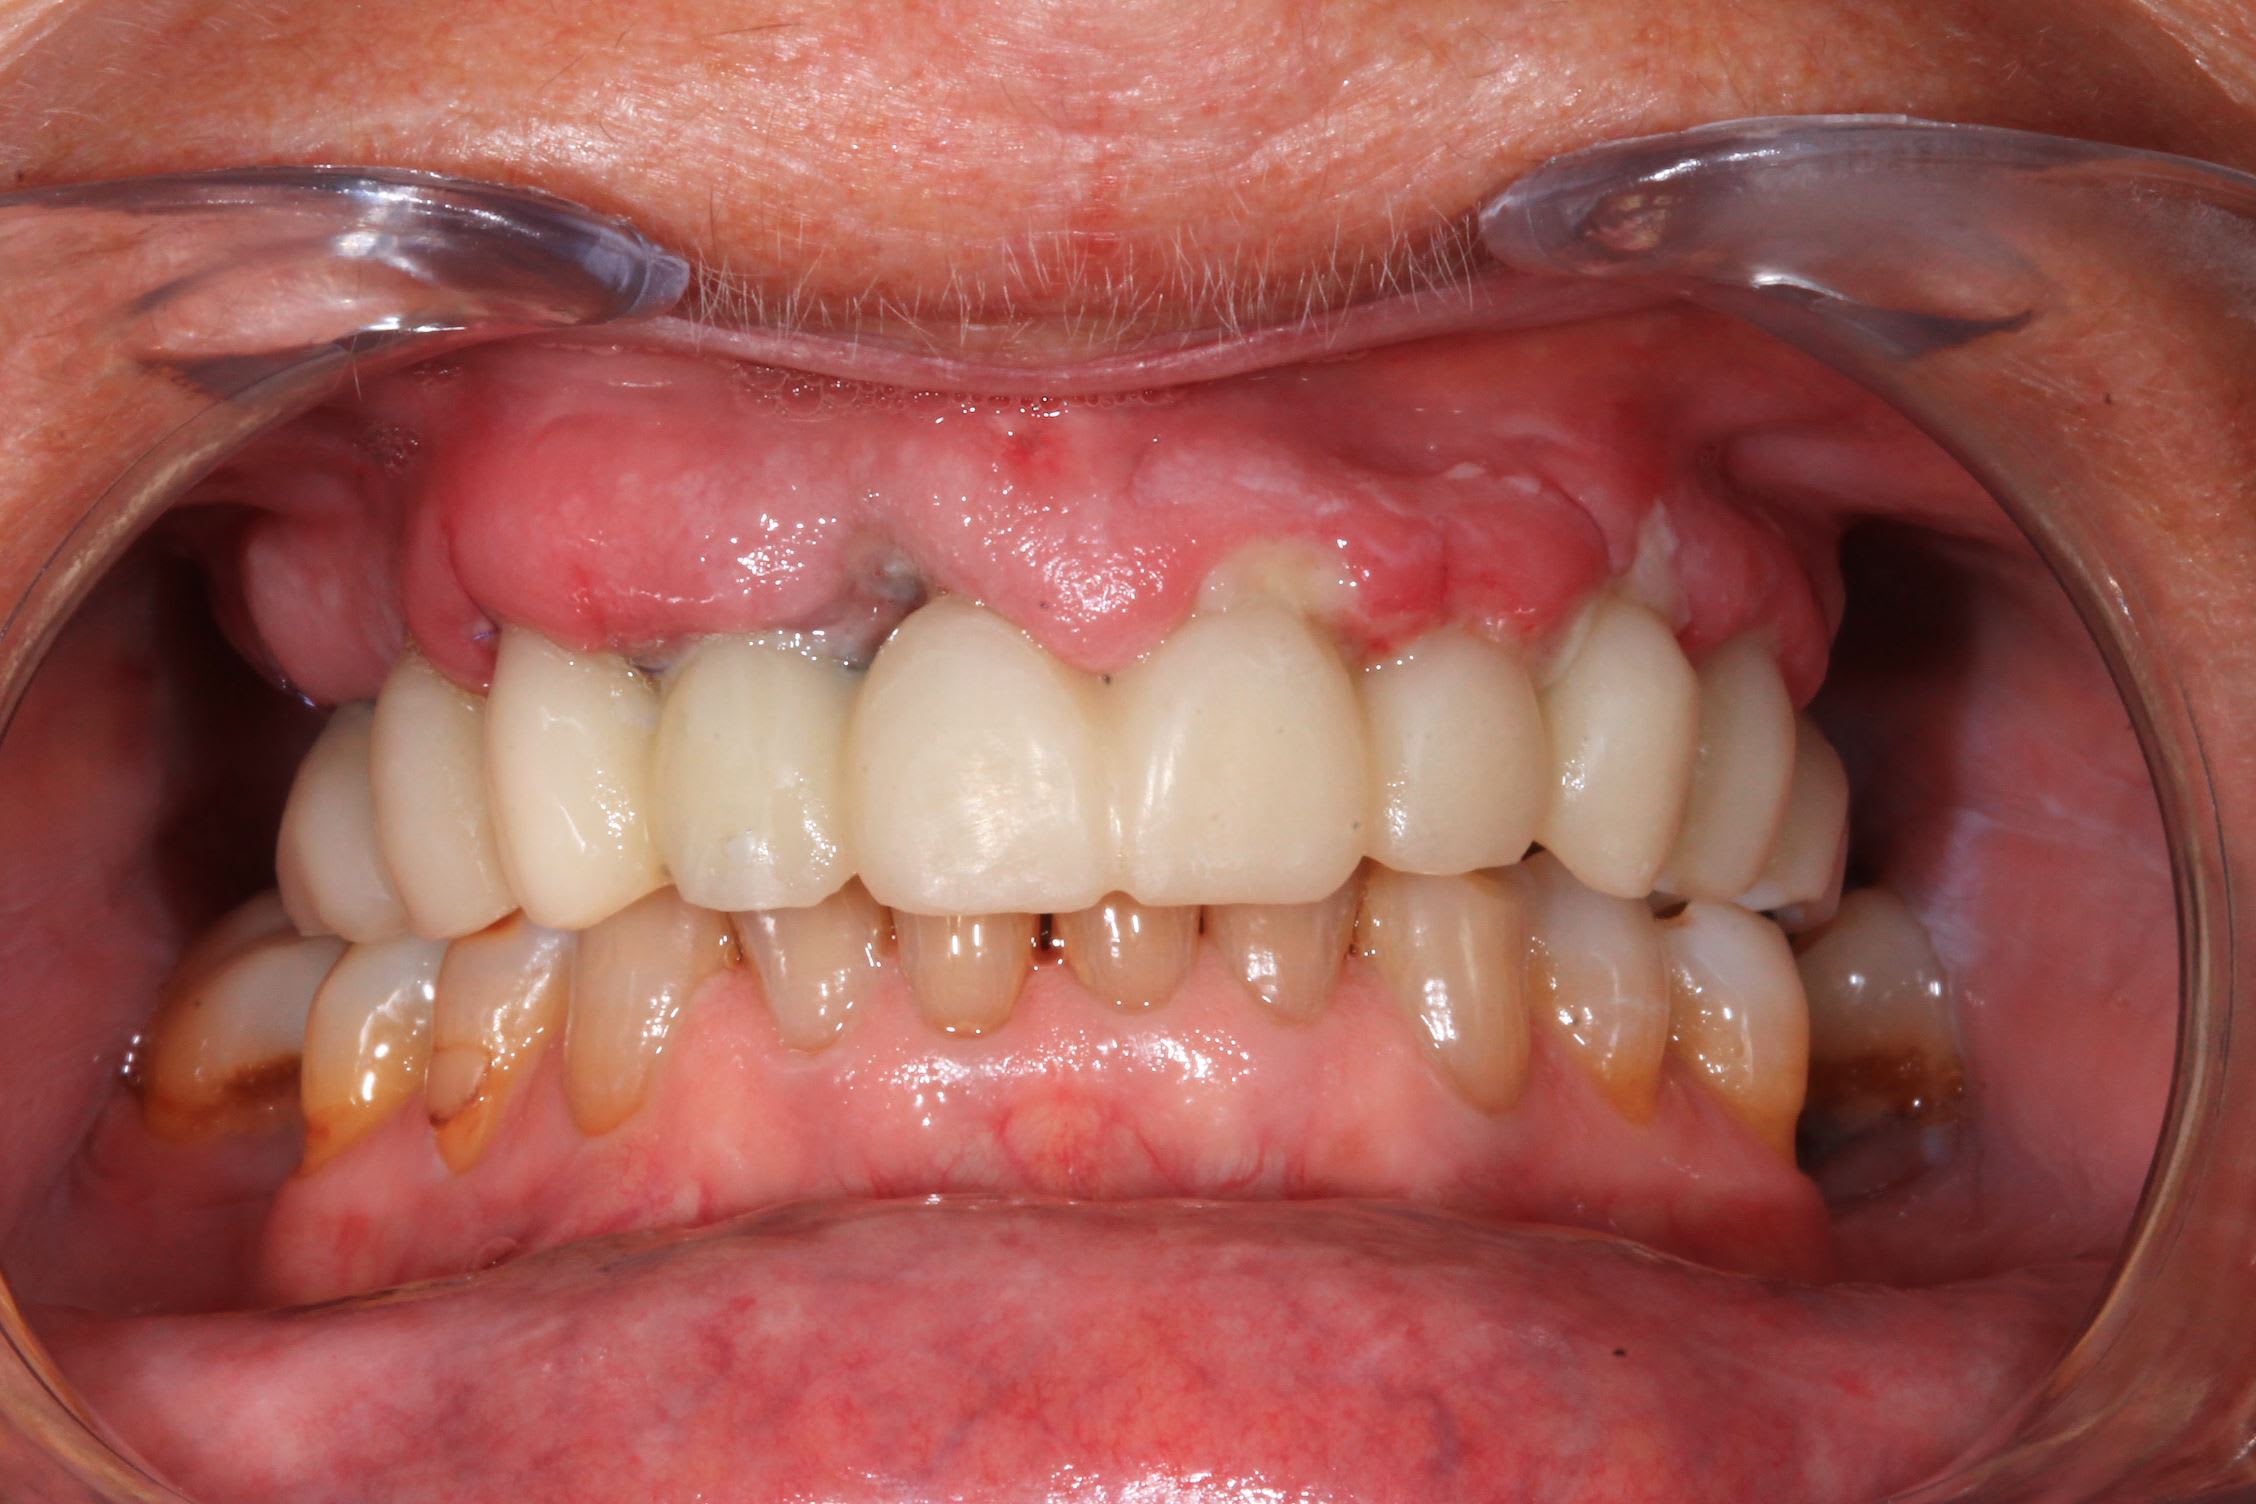

Le cas de la semaine derniere : implants super stable. Premier coup de bistouri a 9h45, patiente sortie à 13h. J'ai galéré avec un satané apex cassé et des canines rebelles : presque 3/4 h pour les extractions !

la suite. Photo post op immédiate et a trois jours.